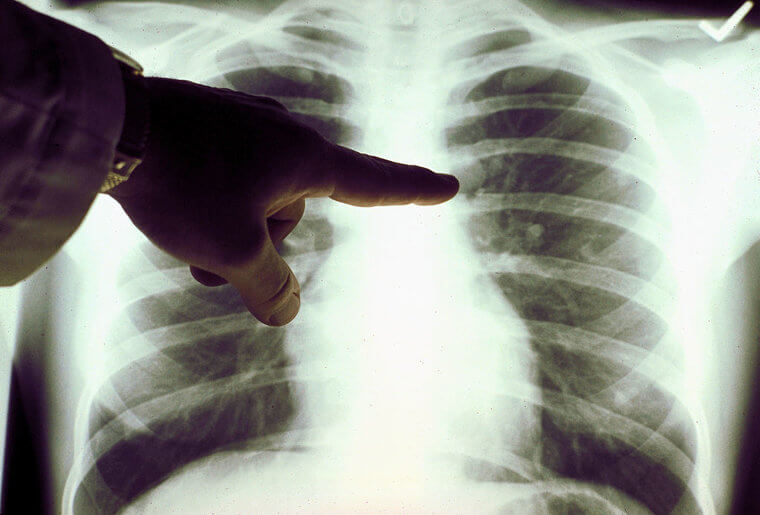

The Human Body Is A Hospitable Host To More Than Just Parasites

It is all fun and games until a plant decides to take up residence in your body. There are not a lot of cases documented in which people have been found with plants growing inside of them, but it does happen. One man in Massachusetts, by the name of Ron Sveden, had been feeling unwell and presenting with cancer symptoms. After a quick x-ray, the culprit was found. A pea seed had taken root in his lung and started to grow.

In another instance, a Russian man named Artyom Sidorkin had also presented with symptoms similarly found with cancer. For him, he had a tiny fir tree growing in his lung. The moral here is to never inhale seeds.